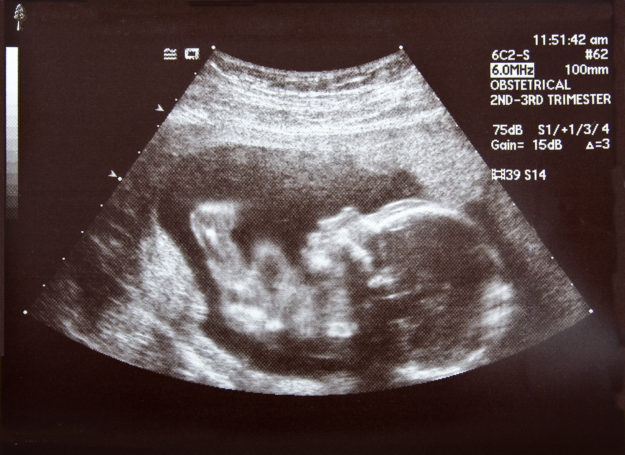

The ACR has deemed effective, June 1, 2014 quality control documentation is required for both ultrasound and breast ultrasound accreditation process. As part of the accreditation application, facilities must demonstrate compliance with the ACR requirements for QC by providing: Report from the most recent annual survey performed by the medical physicist or designee Documentation of…